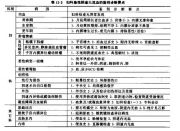

| 2021年7月26日 (一) 20:03 | 药疹与感染性皮疹的比较.jpg (文件) |  |

45 KB | Uploaded with SimpleBatchUpload | 3 |